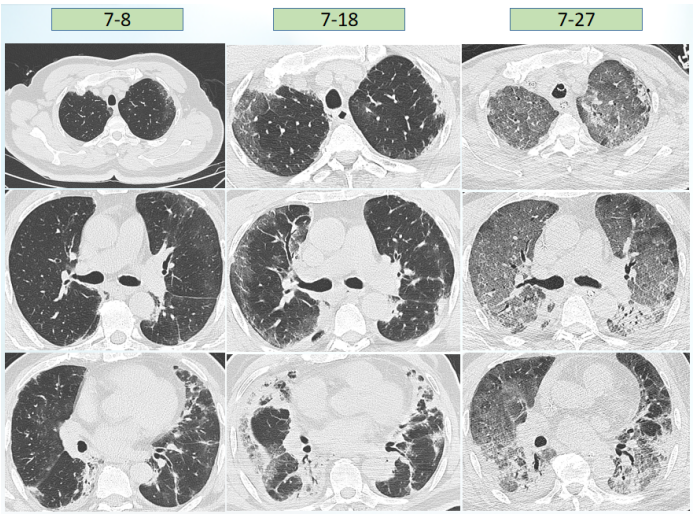

患者入科后体温相对正常,但在7月23日体温升高,考虑当时予以大剂量激素治疗,以及患者肺部病变情况,故在原有抗感染基础上加用了磺胺类药物(图2)。图2  患者体温及感染指标变化趋势(7月19-25日)胸部CT:7月23日在ECMO支持下复查患者胸部CT,发现感染较前加重(图3)。

根据上述病原学结果,在7月28日患者出现发热后,考虑鲍曼不动杆菌感染可能性大,遂加用替加环素,患者体温下降,但至7月30日,患者体温再次升高,白细胞计数逐渐升高。结合气管镜和mNGS回报结果,考虑此时可能出现肺炎克雷伯菌感染,遂加用头孢他啶阿维巴坦,患者体温逐渐下降。8月4日ECMO撤机。患者撤离ECMO后,体温再次升高,考虑鲍曼不动杆菌感染,在原治疗方案基础上加用头孢哌酮舒巴坦(图7)。图7  患者体温及感染指标变化趋势(7月26日-8月8日)撤离ECMO后,复查患者胸部CT可见肺部病变控制较好,但8月27日发现患者肺部出现新的感染(图8)。加用头孢他啶阿维巴坦和头孢哌酮舒巴坦后,白细胞呈下降趋势,但患者体温仍不稳定,时有波动,遂联用多黏菌素(雾化),此后,患者白细胞逐渐趋于正常(图9)。图9  患者体温及白细胞计数变化趋势(8月9-22日)治疗回顾